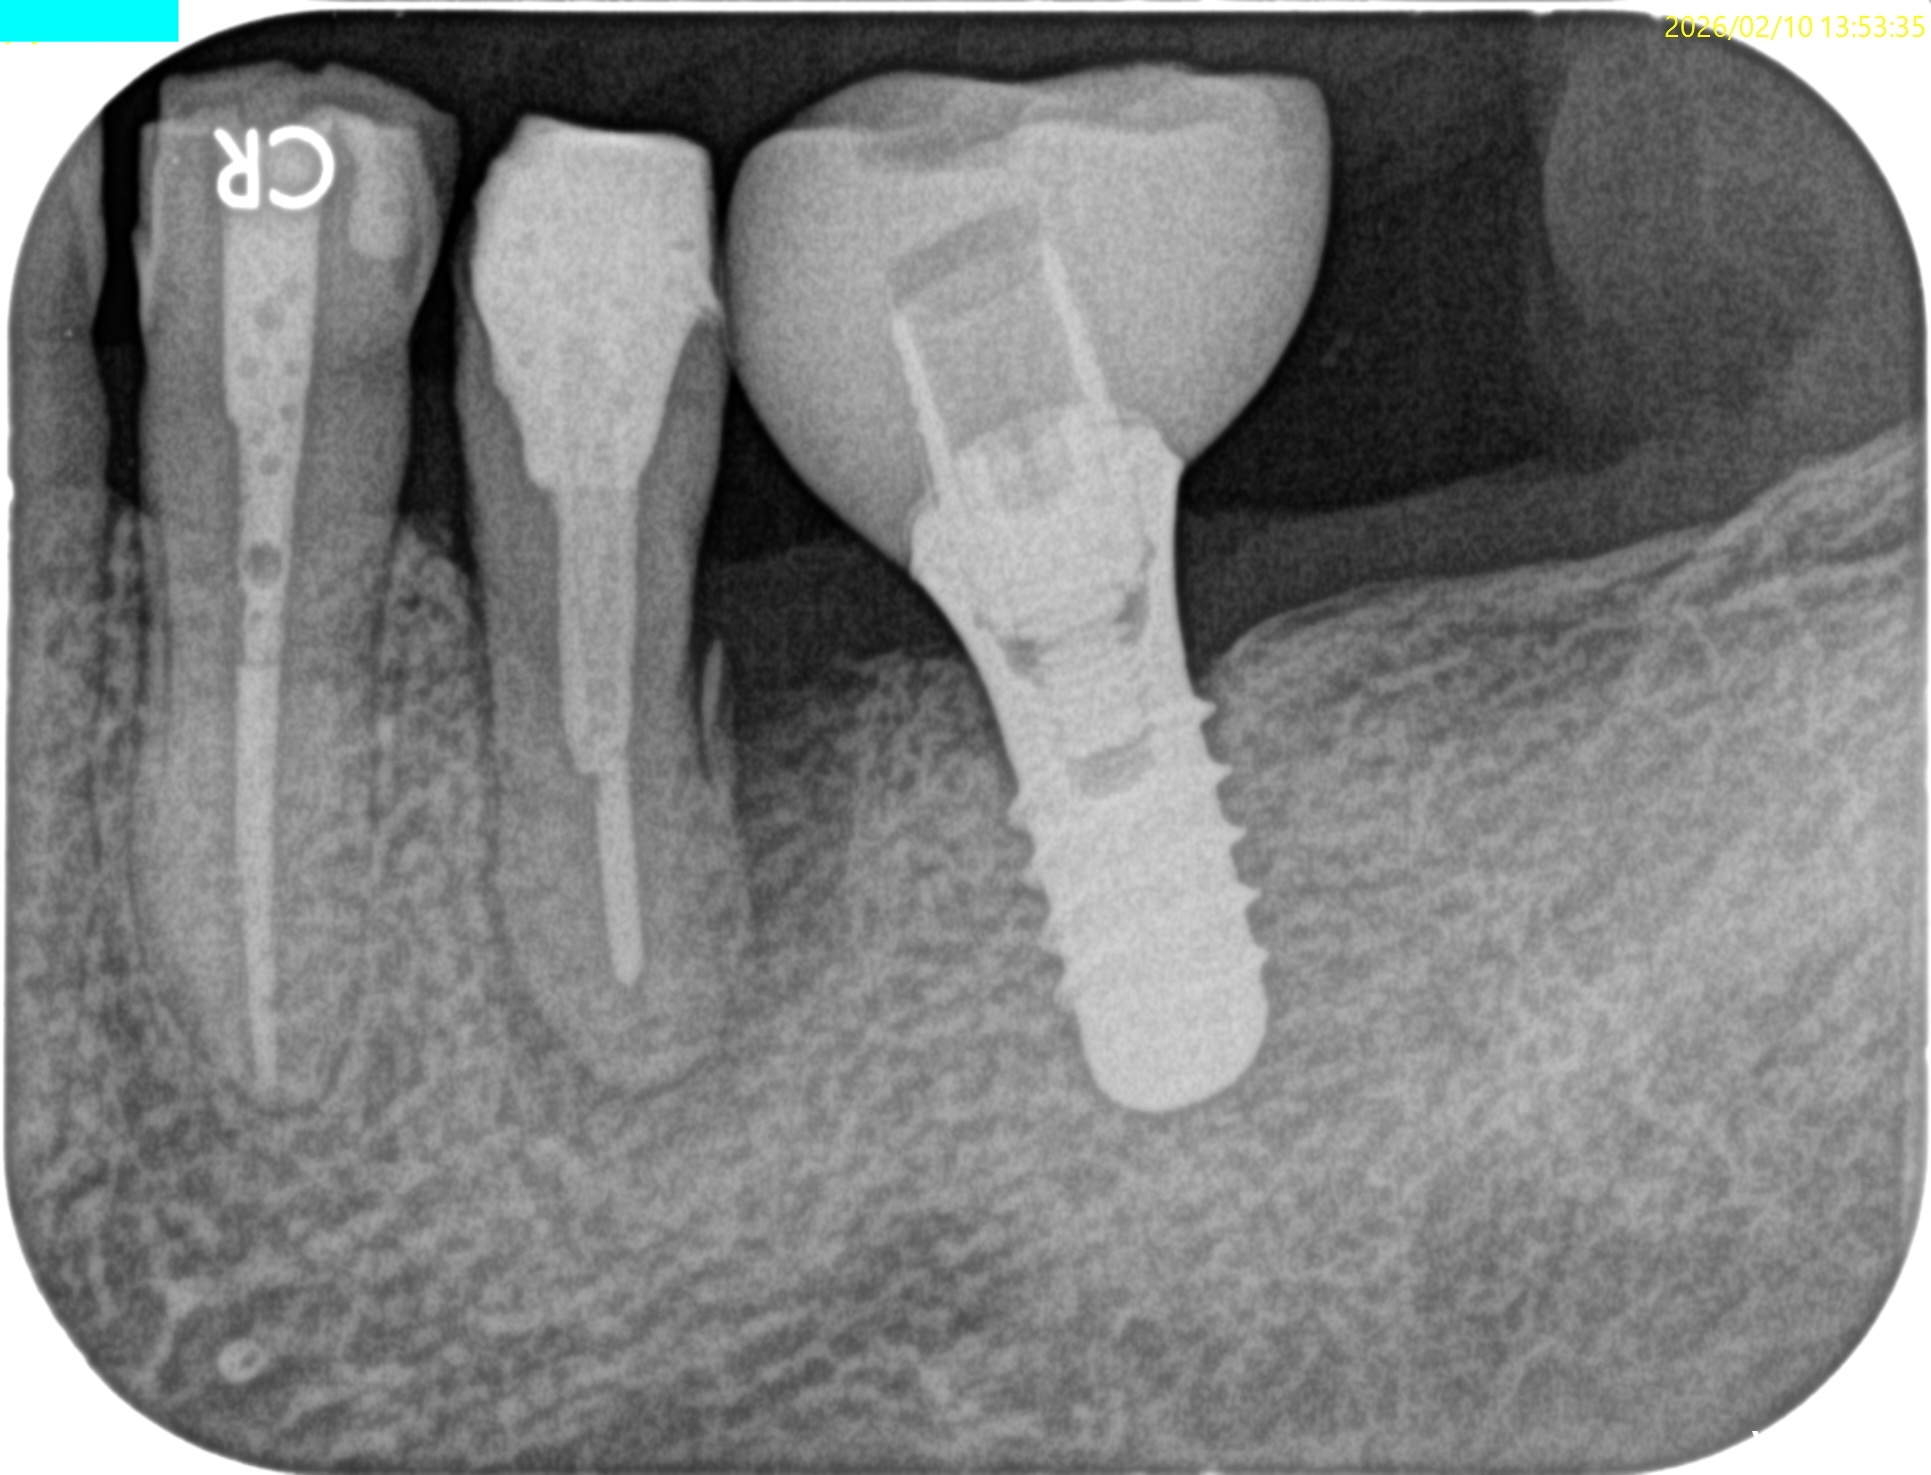

Pre-op Endo test(2026.2.10)

#20は長いピンが装着されており除去に著しく長い時間がかかることが予想される。

まさにこのケースがそれに該当する。

スクリューピンの除去には相当時間がかかるとわかる。